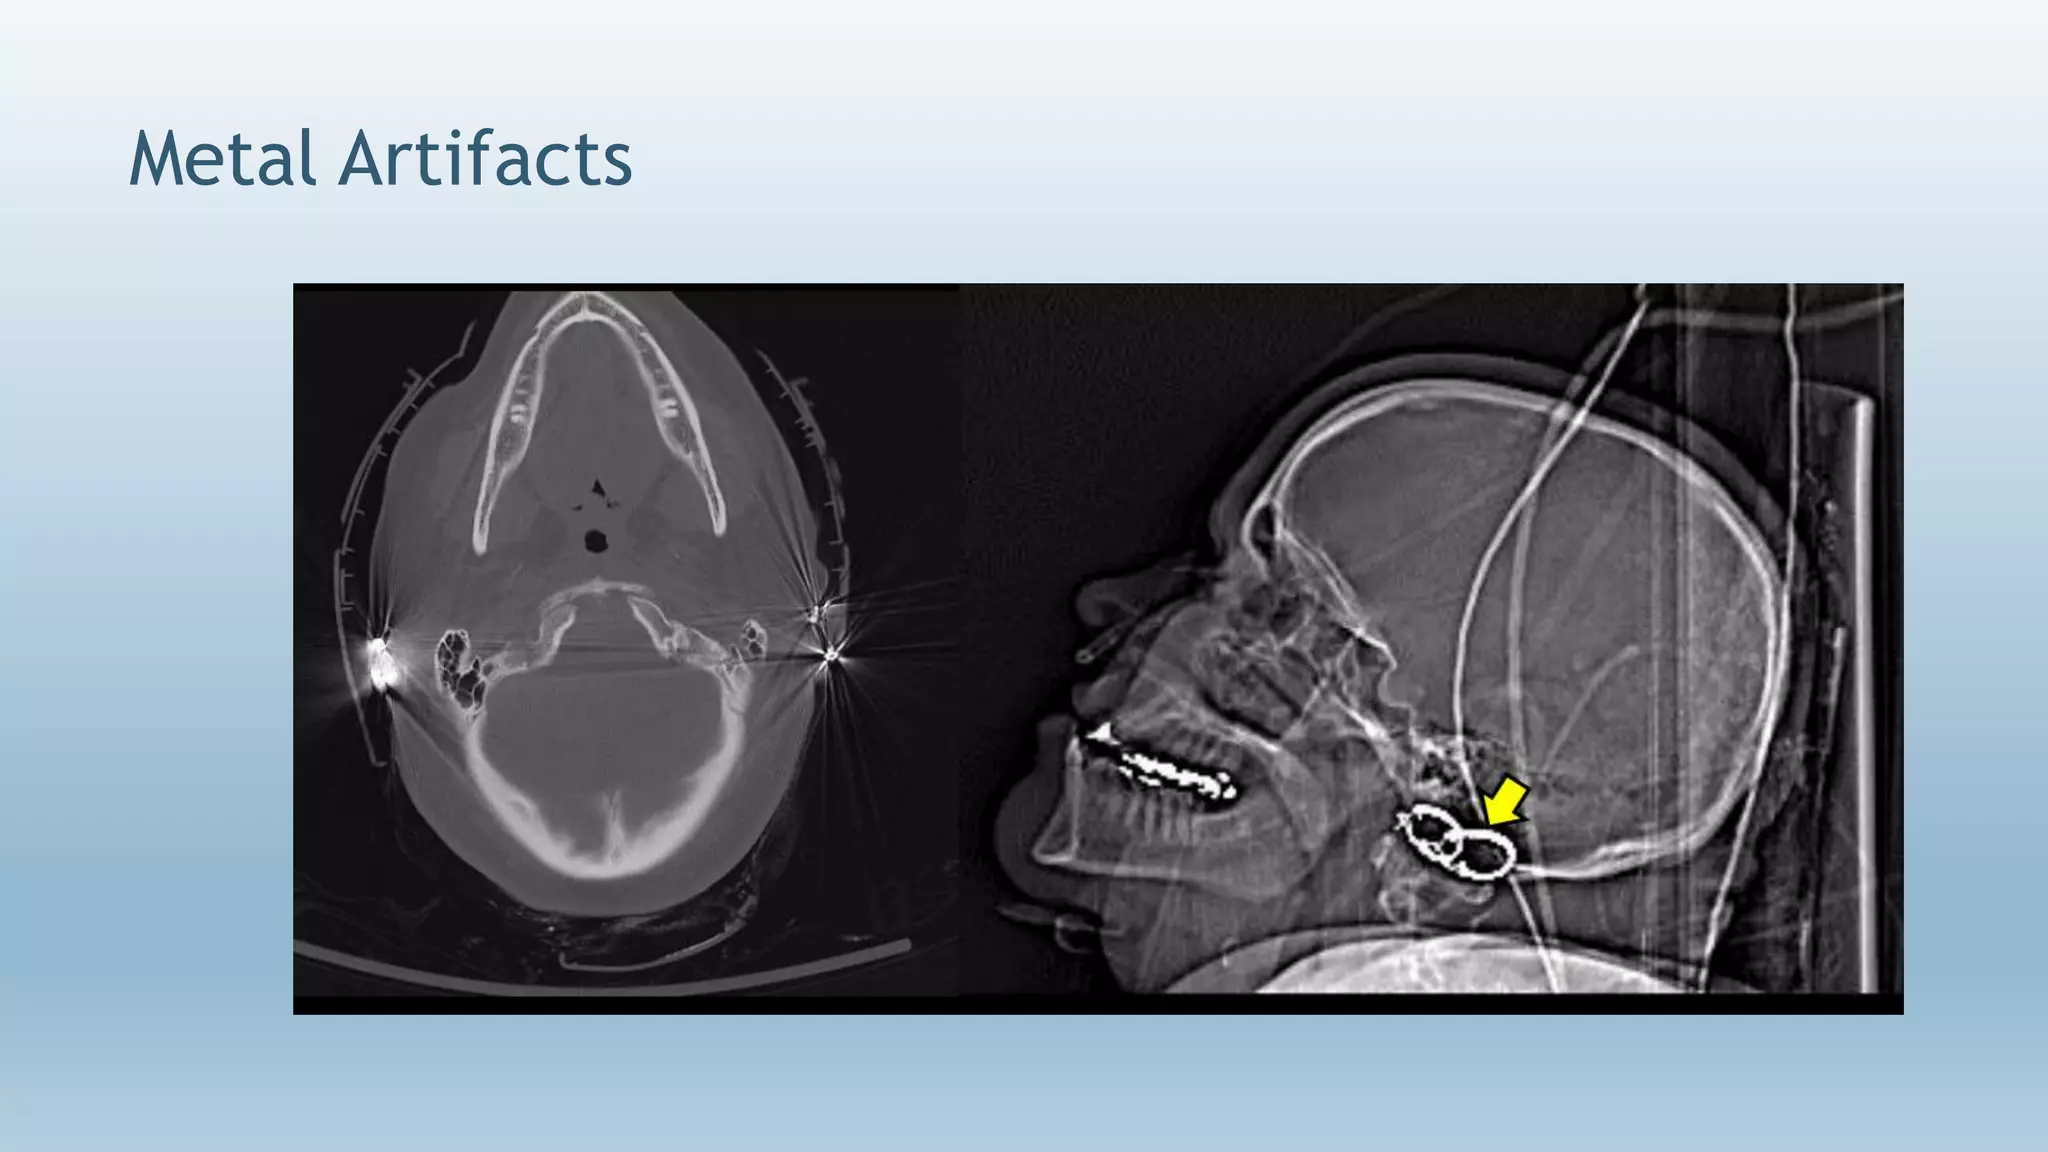

Metal Artifacts

 Manifest itself as “star streaking” artifact.

 It’s caused by presence of metallic objects inside or

outside the patient.

 Metallic object absorbs the photons causing an incomplete

attenuation profile.

 Reduction methods:-

 A. By operator :-

 Taking off removable metal objects before scanning

 Use of gantry angulation

 Increase technique (kv)

 Use thin slices